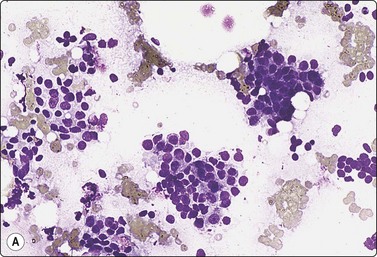

image image

Fig. 7.29 Benign phyllodes tumor

(A) Huge, slowly growing breast mass in a 40-year-old woman; (B) FNB smears were cellular, dominated by dispersed cells with bare oval or plump spindle nuclei (MGG, HP).